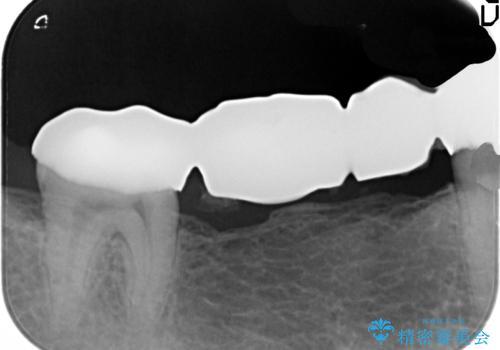

- 右下に入れた長いブリッジが噛むといたみ、改善を希望され来院されました。

長いブリッジは支台となる歯の過大な負担となることが多く、歯の破折や揺れ・痛みの原因となり得ます。